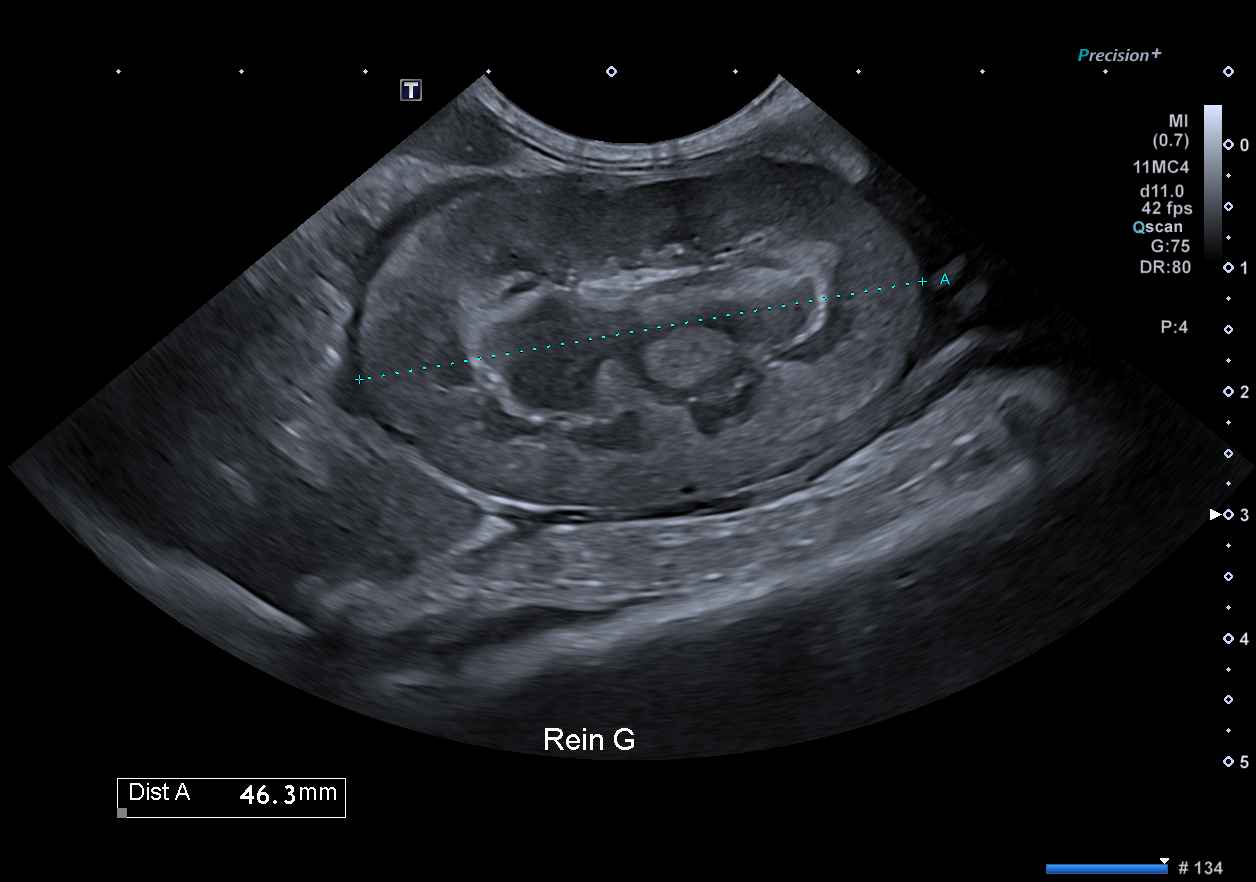

La PIF, maladie infectieuse provoquée par un coronavirus félin pathogène (FIPV) issu de la mutation interne d'un coronavirus entérique félin bénin (FECV), est une véritable problématique particulièrement chez les jeunes chats issus de collectivités avec une évolution toujours fatale en l'absence de traitement efficace.